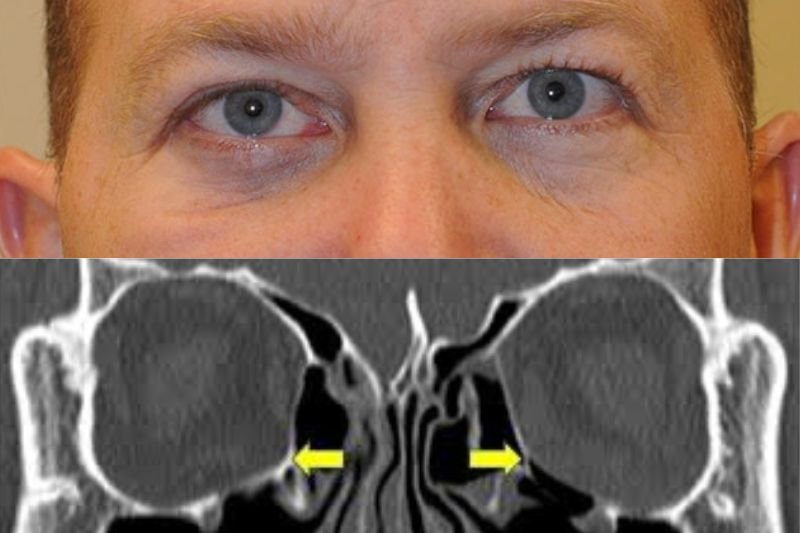

Orbital Fracture Repair

Orbital fracture repair restores damaged eye socket, improving vision, facial structure, and appearance.